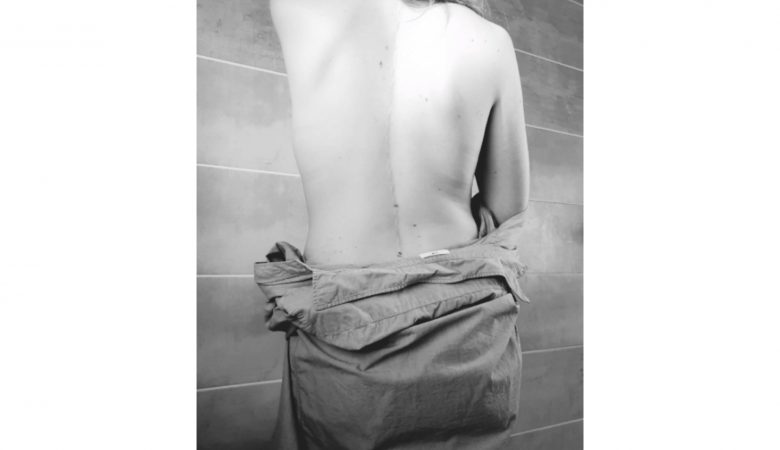

La scoliose est une déviation sinueuse de la colonne vertébrale dans les trois plans de l’espace: inclinaison dans le plan frontal, rotation des vertèbres dans le plan horizontal et inversion des courbures dans le plan sagittal. Il s’agit d’une déformation non réductible, contrairement à l’attitude scoliotique. Une déviation du rachis est considérée comme une scoliose …